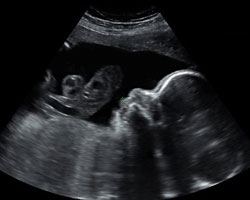

Já de 28 semanas! Queres ver como é um bebé em desenvolvimento nesta altura da gravidez? Aqui tens uma ecografia e um fantástico vídeo para que o vejas em movimento. Não percas!

Ecografia de 28 semanas